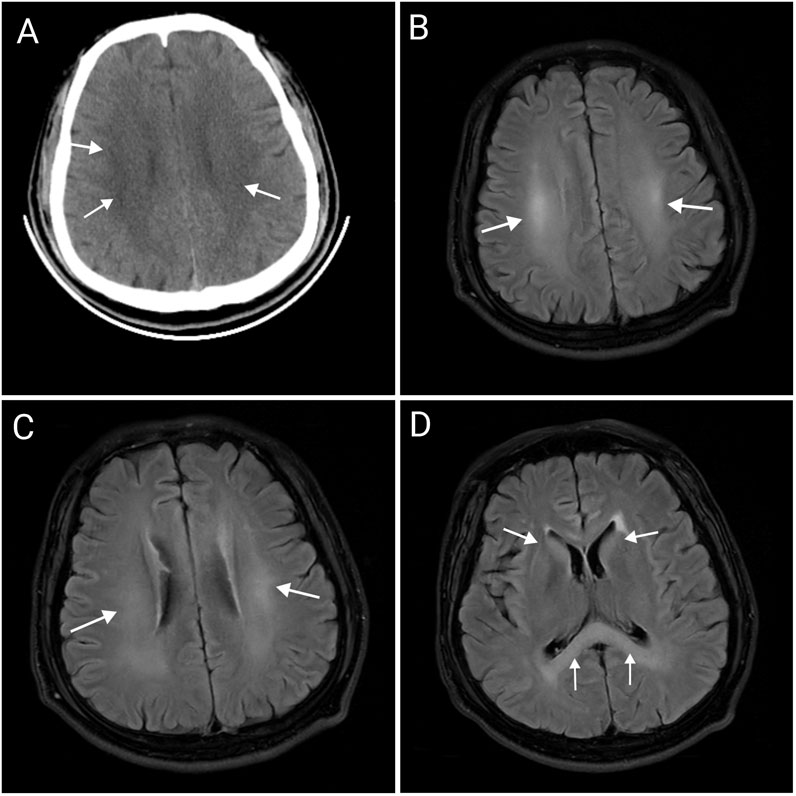

Background: 4-Methylsulfonyl-benzonitrile is an organic compound used in organic synthesis with applications in medicine, dye, and pesticide production. However, its toxicological characteristics in humans remain poorly understood, with no previously reported cases of poisoning. Case Presentation: This report describes a 33-year-old male who developed severe toxic encephalopathy and peripheral neuropathy following occupational exposure during herbicide production. The patient worked without adequate personal protective equipment in a workshop where he was intermittently exposed to organic solvents, including 4-methylsulfonyl-benzonitrile, over several months. He initially presented with dizziness, slurred speech, and mental deterioration, which progressed to impaired consciousness and respiratory failure requiring mechanical ventilation. Blood analysis revealed an initial 4-methylsulfonyl-benzonitrile concentration of 734 ng/mL upon initial testing, decreasing to 76 ng/mL, and becoming undetectable within ten days. Magnetic resonance imaging (MRI) showed diffuse symmetric abnormalities in the corpus callosum, bilateral basal ganglia, corona radiata, and centrum semiovale. Electromyography confirmed sensorimotor peripheral neuropathy. Intervention and Outcome: The patient received comprehensive treatment including mechanical ventilation, organ protection, neurotrophic therapy, anti-infective therapy, and nutritional support. After 28 days of hospitalization, he was discharged with significant improvement— conscious, oriented, and with normalized speech, although mild numbness in the limbs persisted. Conclusion: This case demonstrates that 4-methylsulfonyl-benzonitrile poisoning can induce both toxic encephalopathy and peripheral neuropathy. The findings highlight an urgent need to strengthen safety monitoring and safety training in chemical manufacturing enterprises.